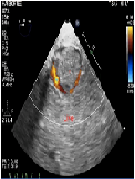

Use of Transesophageal Echocardiography During Cesarean Section in A Parturient with Inferior Vena Cava Thrombosis:A Case Report

Peter M. Huynh*, Quy Tran, Hany Rayan, Marc Huh, QuayQuyTran, Clinton Kakazu

Anesthesia and Medical Practice Journal